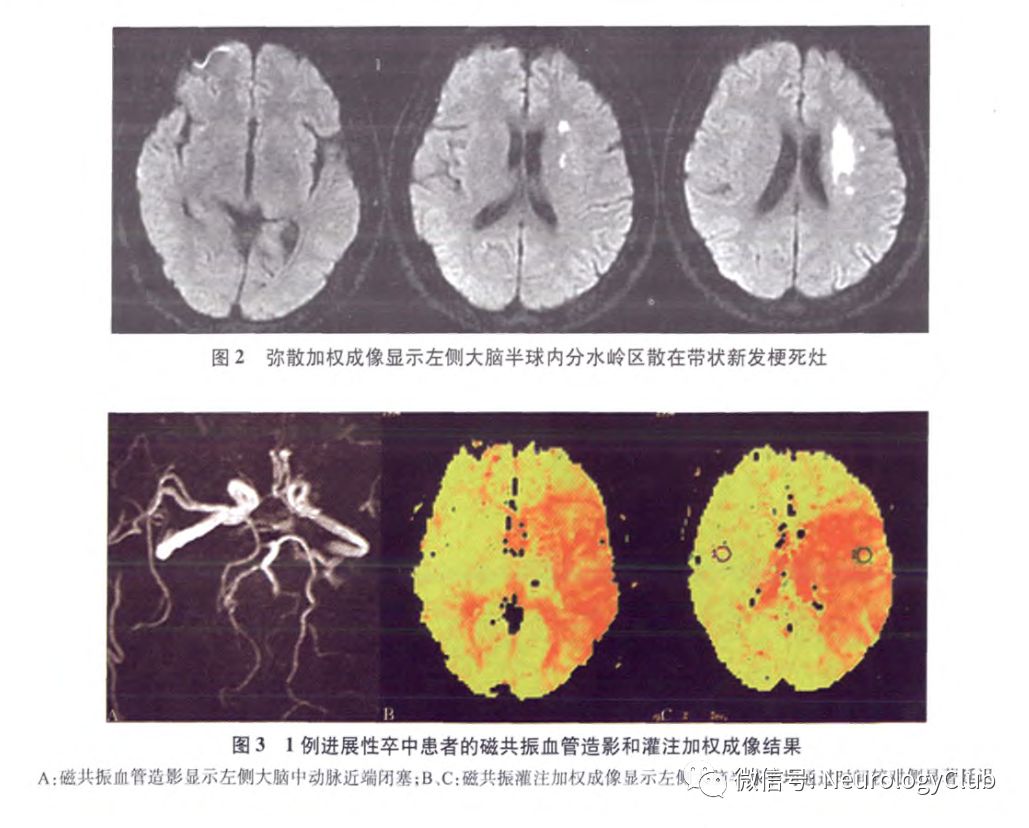

另有研究表明,分水岭梗死往往预示着END的发生,尤其是内分水岭梗死后者多表现为多发性梗死,且通常伴有严重的大动脉狭窄,血流动力学障碍可能是其最主要的发病机制。Kim等报道了12例伴有颅内动脉重度狭窄的小卒中患者,根据梗死部位和分布特点,将急性期DWI显示的梗死灶分为4种模式:内分水岭梗死、皮质分水岭梗死、皮质支梗死和深穿支动脉梗死,结果显示,END更多见于内分水岭梗死。随后的一项研究共纳入了95例伴有大脑中动脉或基底动脉中到重度狭窄的小卒中或短暂性脑缺血发作(transient ischemic attack,TIA)患者,END发生率为14.7%,logistic回归分析显示,分水岭梗死是END的独立预测因素(P=0.004)。虽然分水岭梗死的病理生理学机制仍存在争议,但一般认为低灌注与微栓子共同导致了分水岭梗死,低灌注导致的微栓子清除障碍在分水岭区更为多见,易出现卒中进展。因此,早期神经影像学发现,尤其在DWI显示病灶分布散在,可能有助于预测END的发生(图2-4)。